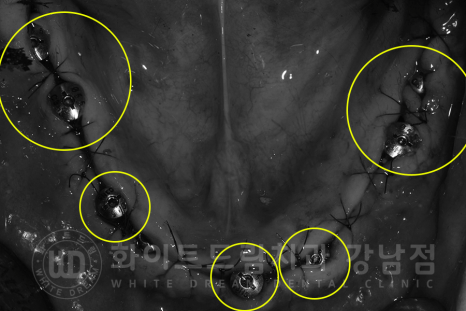

환자분의 남아있던 치아들을 모두 발치한 사진입니다.

치아 뿌리 주변에 거뭇거뭇하게 치석들이 굉장히 많이 있는 것이 보이시나요?

이렇게 치아 부분까지, 잇몸 안쪽에 위치해있는 치석을 '치은연하치석'이라고 합니다.

치주염을 유발하는 주된 원인들이죠.